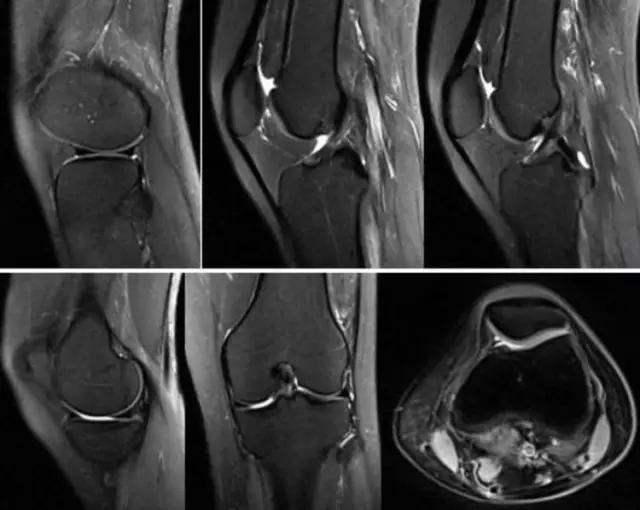

地中海贫血与白血病均为血液系统的问题,主要表现在骨髓,疾病的发病机理有别,MRI表现也不相同;我们可能不是很熟悉这些疾病,也能够从MRI发现区别。图1:正常膝关节 图2:地中海贫血 图3:白血病

利用自身对比——

我们可能都不熟悉T1、T2,怎么办?当我们发现有问题后,利用照片上图像的对比,推测病变的可能也是一种诊断方法。病例:黄XX,女,39岁,左膝关节反复交锁1年。图1:肿物信号与骨信号一样图2:肿物信号与骨信号一样图3:肿物信号与骨信号不一样 肿物应该与骨相关,但不是骨性,推断:膝关节滑膜软骨瘤。手术后得到证实。